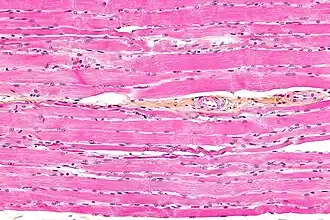

Striated muscle tissue is a muscle tissue that features repeating functional units called sarcomeres. Under the microscope, sarcomeres are visible along muscle fibers, giving a striated appearance to the tissue. The two types of striated muscle are skeletal muscle and cardiac muscle.

Skeletal muscle includes skeletal muscle fibers, blood vessels, nerve fibers, and connective tissue. Skeletal muscle is wrapped in epimysium, allowing structural integrity of the muscle despite contractions. The perimysium organizes the muscle fibers, which are encased in collagen and endomysium, into fascicles. Each muscle fiber contains sarcolemma, sarcoplasm, and sarcoplasmic reticulum. The functional unit of a muscle fiber is called a sarcomere.[2] Each muscle cell contains myofibrils composed of actin and myosin myofilaments repeated as a sarcomere.[3] Many nuclei are present in each muscle cell placed at regular intervals beneath the sarcolemma.

Unlike skeletal and cardiac muscle tissue, smooth muscle tissue is not striated since there are no sarcomeres present. Skeletal muscles are attached to some component of the skeleton, and smooth muscle is found in hollow structures such as the walls of intestines or blood vessels. The fibres of striated muscle have a cylindrical shape with blunt ends, whereas those in smooth muscle are spindle-like with tapered ends. Striated muscle tissue has more mitochondria than smooth muscle. Both smooth muscle cells and cardiac muscle cells have a single nucleus, and skeletal muscle cells have many nuclei.[6]